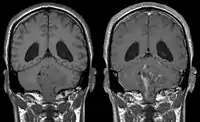

An ependymoma is a tumor that arises from the ependyma, a tissue of the central nervous system. Usually, in pediatric cases the location is intracranial, while in adults it is spinal. The common location of intracranial ependymomas is the fourth ventricle. Rarely, ependymomas can occur in the pelvic cavity.

Ependymomas make up about 5% of adult intracranial gliomas and up to 10% of childhood tumors of the central nervous system (CNS). Their occurrence seems to peak at age 5 years and then again at age 35. They develop from cells that line both the hollow cavities of the brain and the canal containing the spinal cord, but they usually arise from the floor of the fourth ventricle, situated in the lower back portion of the brain, where they may produce headache, nausea and vomiting by obstructing the flow of cerebrospinal fluid. This obstruction may also cause hydrocephalus. They may also arise in the spinal cord, conus medullaris and supratentorial locations.[4] Other symptoms can include (but are not limited to): loss of appetite, difficulty sleeping, temporary inability to distinguish colors, uncontrollable twitching, seeing vertical or horizontal lines when in bright light, and temporary memory loss. It should be remembered that these symptoms also are prevalent in many other illnesses not associated with ependymoma.

Although some ependymomas are of a more anaplastic and malignant type, most of them are not anaplastic. Well-differentiated ependymomas are usually treated with surgery. For other ependymomas, total surgical removal is the preferred treatment in addition to radiation therapy. The malignant (anaplastic) varieties of this tumor, malignant ependymoma and the ependymoblastoma, are treated similarly to medulloblastoma but the prognosis is much less favorable. Malignant ependymomas may be treated with a combination of radiation therapy and chemotherapy. Ependymoblastomas, which occur in infants and children younger than 5 years of age, may spread through the cerebrospinal fluid and usually require radiation therapy. The subependymoma, a variant of the ependymoma, is apt to arise in the fourth ventricle but may occur in the septum pellucidum and the cervical spinal cord. It usually affects people over 40 years of age and more often affects men than women.[7]